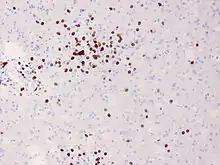

In Rasmussen's encephalitis, there is chronic inflammation of the brain, with infiltration of T lymphocytes into the brain tissue. In most cases, this affects only one cerebral hemisphere, either the left or the right. This inflammation causes permanent damage to the cells of the brain, leading to atrophy of the hemisphere; the epilepsy that this causes may itself contribute to the brain damage. The epilepsy might derive from a disturbed GABA release,[2] the main inhibitory neurotransmitter of the mammalian brain.

Brain biopsy can provide very strong confirmation of the diagnosis, but this is not always necessary.[9][10]